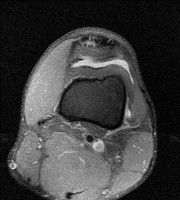

무릎 mri 간단히 봐주실 수 있으시나요 ㅠㅠ

안녕하세요 8년전 십자인대 수술하고 최근 무리한 운동에 무릎 불편감이 생겨서

mri 찍었습니다.

진단결과는 첫 찍은 병원에서 활액막염 이라는 진단을 받았습니다. 혹시 봐주실 수 있으실까요?

올라온 MRI가 단편적이라서 정확한 진단에 어려움이 있지만 십자인대에는 큰 이상이 있지는 않은것 같으며, 무릎관절내 물이 있는 것으로 보아 활액막염의 진단이 맞을 것 같습니다.

하지만 단편적인 영상이기 때문에 촬영병원에서 정확한 판독지 등을 받으시는 것이 좋겠습니다.